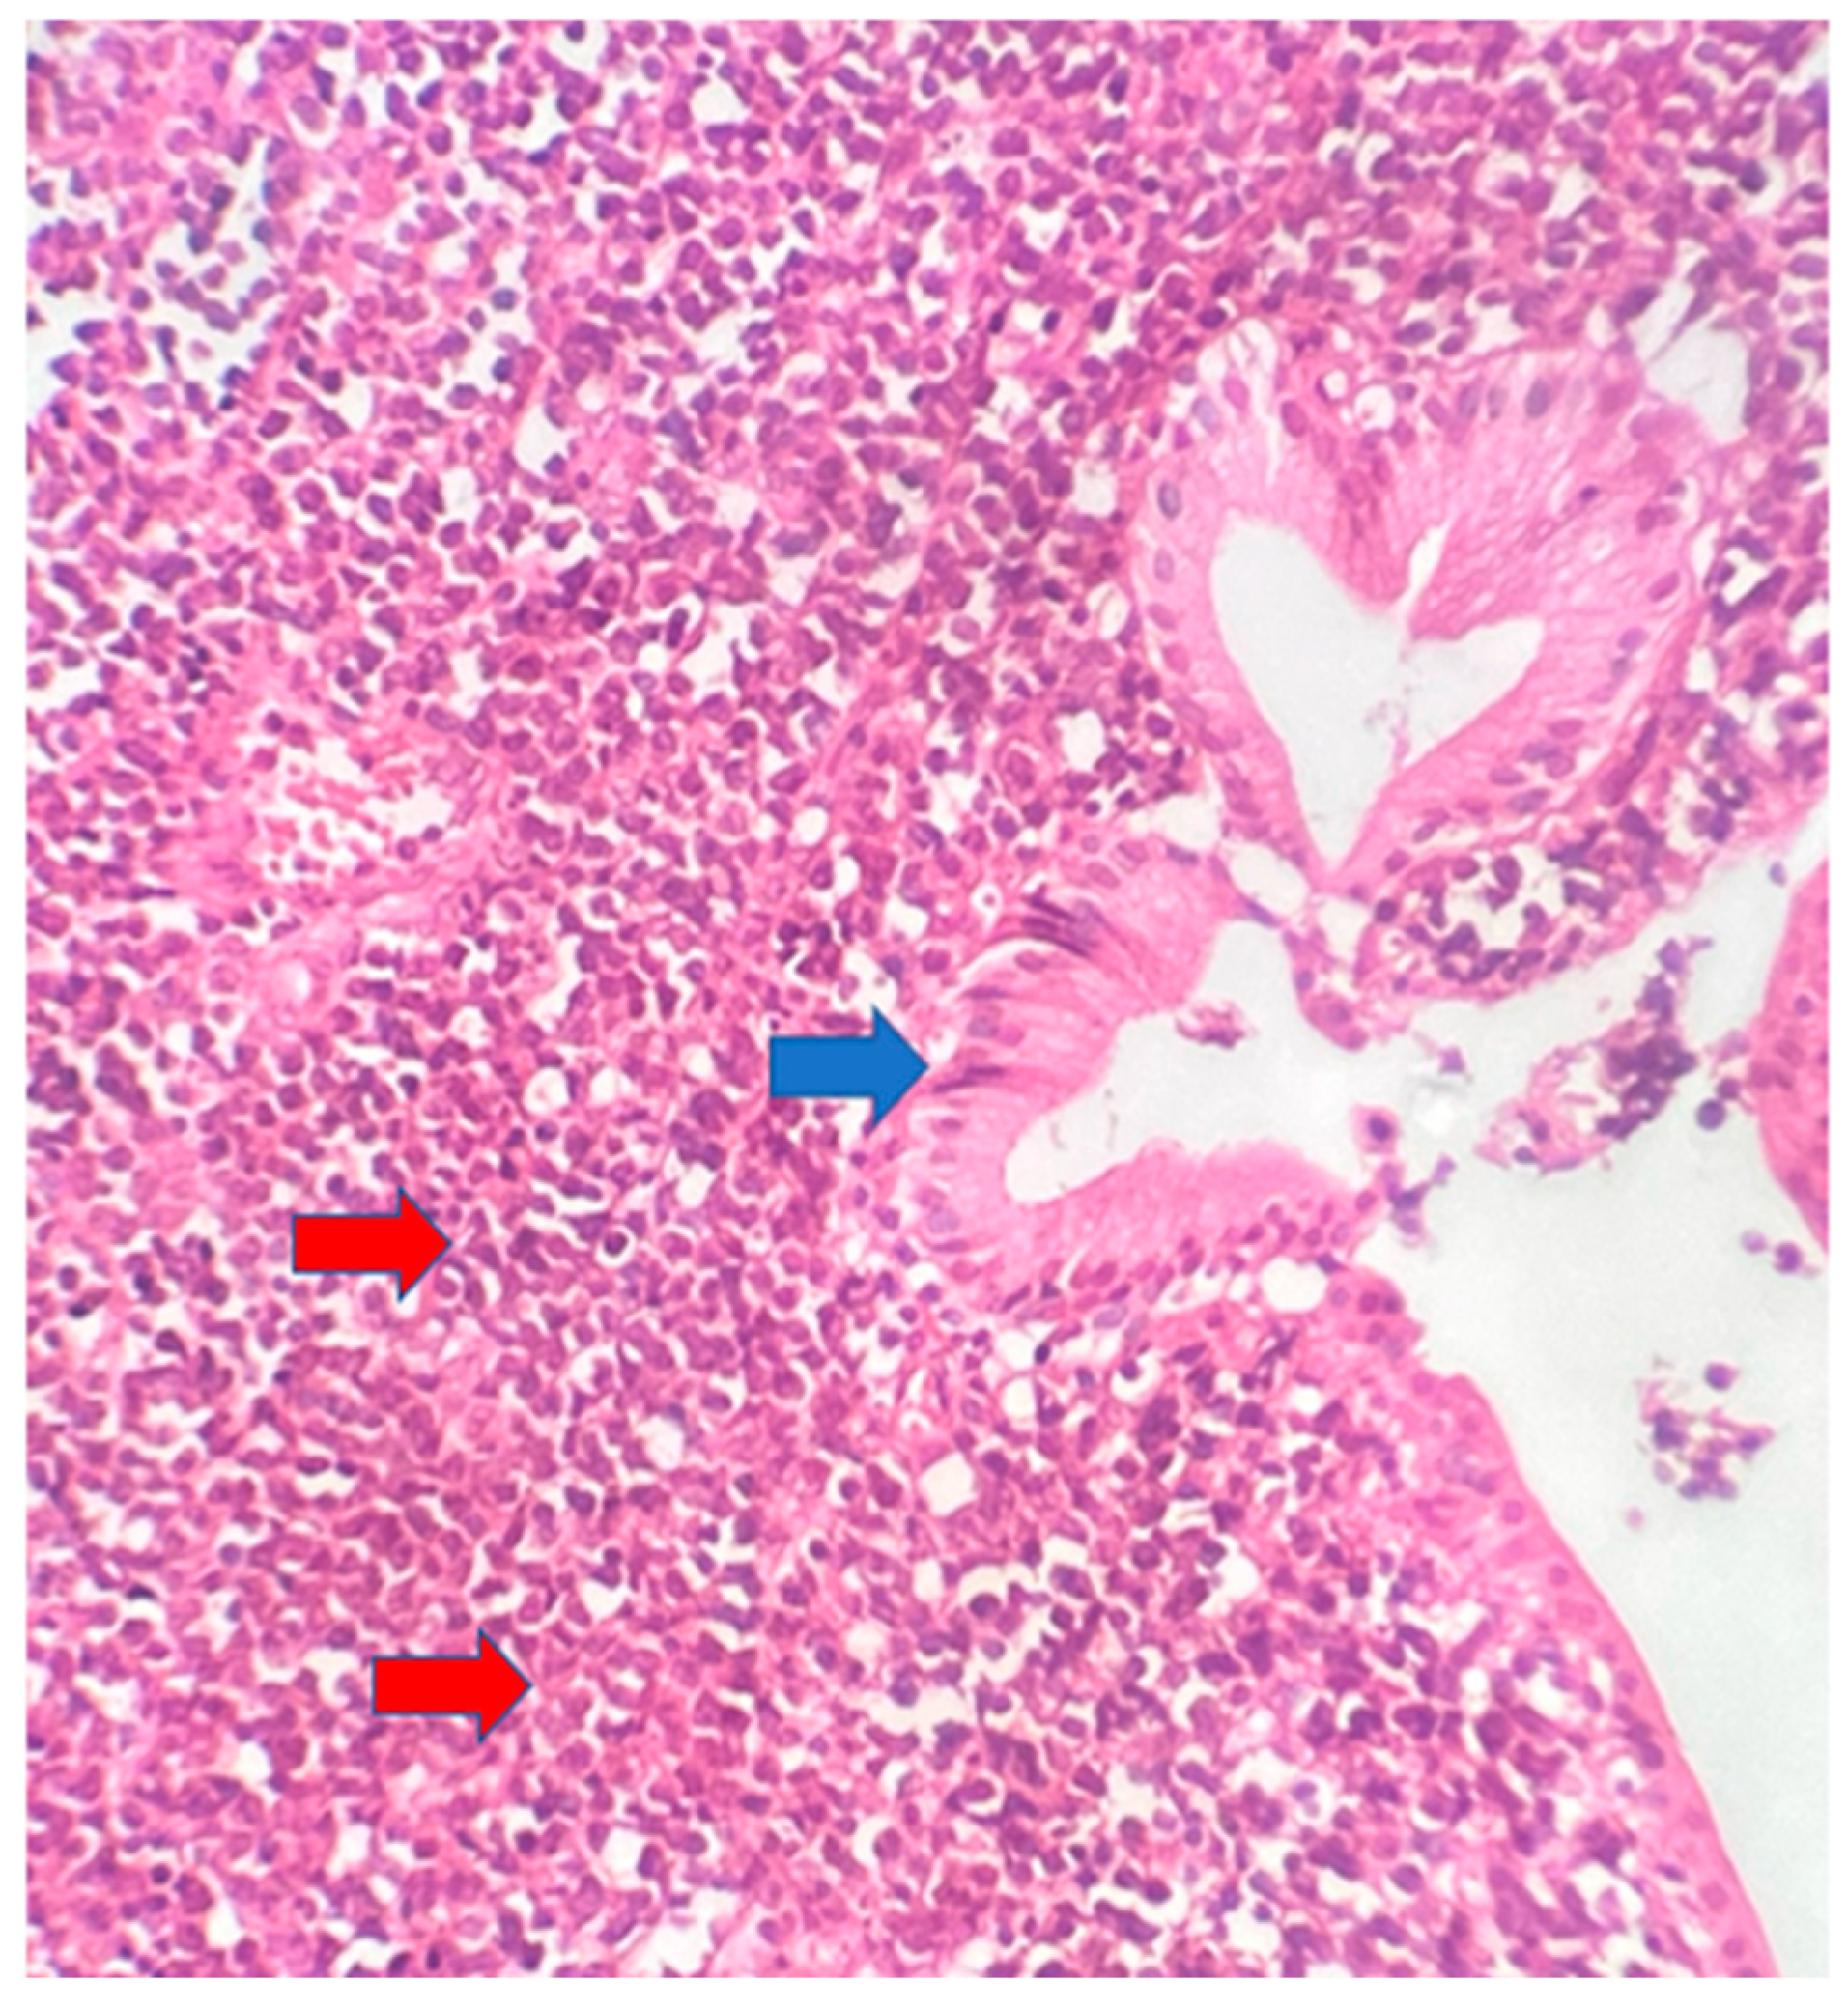

The postoperative histopathological examination of the resected specimen occurred on 07/16/99 at the Department of Pathology of Clementino Fraga Filho University Hospital (HUCFF/UFRJ). The macroscopic examination showed a gallbladder measuring 4 cm × 1.0 cm × 0.9 cm. The serosa was opaque, and the wall thickened and became white, with a firm consistency. The specimen was re-evaluated by a hematopathologist on 08/19/22 (C.B.M), who confirmed the diagnosis of BL through microscopic analysis and immunohistochemical study according to WHO, 2022 [13]. Morphological analysis revealed diffuse proliferation of intermediate-sized cells, with small nucleoli invading and destroying the bladder wall, with a high apoptotic and mitotic index. The neoplastic cells showed positivity for CD20, CD10, Ki67 99%, and EBER by in situ hybridization (EBER1) [13,14]. Combined with the patient’s medical history, the final diagnosis was gallbladder BL. This is an AIDS-defining malignancy (ADM), codified as 2A85.6 (BL) according to ICD-11 MMS [15]. There are five photographs of the sample in question below (Figure 1, Figure 2, Figure 3, Figure 4 and Figure 5).

Figure 2. Intermediate-sized cells, with evident nucleoli and diffuse proliferation (red arrows). 40× magnification.